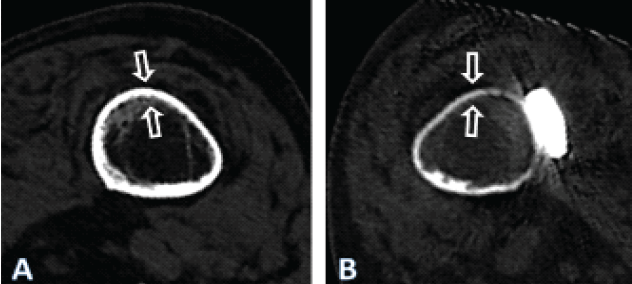

Figure 5: Computed tomography scan images 4 years after fixation of the periprosthetic fracture of the left femur after cemented hemiarthroplasty of the hip in the patient described, illustrating the cross-section at the level of the yellow line in Fig. 1, for both the right (a) and the left (b) femur. Note the general atrophy of the bone of the left femur, compared to the thickness of the cortex of the right femur, which may be considered normal at such age in females, despite immobilization. There nevertheless is a cancellous transformation at the inner cortex of the right femur, typical for endosteal resorption, as expected after prolonged unloading, the patient having never regained walking ability.

As the treating team considered the stem to be stable, with a fracture evaluated as being located distally to the area of fixation (Unified Classification System [UCS] Type C) [17], plate fixation was chosen. Open reduction and internal fixation of the fracture was performed through a subvastus approach, with reduction and fixation by a cable cerclage (Cable System 1.7 mm, DePuy Synthes, Zuchwil, Switzerland) and application of a lateral neutralization plate (non-contact bridging [NCB] Periprosthetic Femur Plate System 18 hole, Zimmer Biomet, Zug, Switzerland), fixated distally with screws and along the level of the stem with further cable cerclages (Cable System 1.7 mm). Postoperatively, the patient was mobilized in a wheelchair, as full weight-bearing was not recommended and as it was not possible to implement partial weight-bearing. Wound healing was uneventful. The radiological follow-up after 8 weeks showed intact material without evidence of loosening (Fig. 1c). Mobilization under full weight-bearing with support by physical therapy was then attempted. Four months postoperatively, the radiological follow-up showed a general atrophy of the cortical bone, which was accentuated at the lateral cortex, underneath the plate (Fig. 1d). Mobilization was hampered due to thigh pain, which had been interpreted to be caused by muscle atrophy. Thus, further physical therapy was recommended. As the impaired mobility caused difficulties attending consultation at the hospital, no further follow-up visits were planned. Due to increasing thigh pain, the patient was readdressed for evaluation by her general practitioner 4 years after the operative treatment of the PPF. Not having been mobilized outside a wheelchair in the meantime, the patient showed bilateral hip and knee flexion contractures. Consequently, she was unable to stand, disregarding the issue of thigh pain. Radiologically, there was now pronounced atrophy of the cortical bone of the femur, particularly of the lateral cortex under the plate (Fig. 1e). An infection was considered unlikely, as there was no pain at rest, as the soft tissues were inconspicuous, as the fracture had healed, and as there were no general symptoms. A single-photon emission computed tomography (CT) showed avascular areas of cortical bone underneath the plate (Fig. 3). The CT better illustrated a general atrophy of the femur with thinning of the bone cortex in comparison to the contralateral femur (Fig. 4 and 5). There was, however, no sign of loosening of the stem. Considering comorbidities, very limited potential for recovery, and the patients’ desire for no more surgery, the option of a revision was rejected, accepting the present situation. The patient died 7 months later.

When applied directly to the bone, the longitudinal groove of the NCB may potentially compromise blood perfusion on a relatively large surface, especially if the edges of the groove compress the periosteum. In the present case, the plate had been applied in direct contact with the bone and with considerable pressure, exerted by the cerclages and conventional, non-locking screws. Cortical bone necrosis due to compression of the periosteal vessels may be avoided if the NCB plate is used as an internal fixator, applied at a distance from the bone. However, this may not be possible if cerclages have to be used to avoid interference of screws with the prosthesis stem and/or cement. While the NCB system offers the possibility to use stub screws as distance holders, this may prove inadequate in such situations. Cerclages are usually necessary in the segment of the underlying stem to achieve and maintain adequate reduction of the bone fragments and stabilize the plate. In case of osteoporosis, stub screws would be prone to being crushed into the bone, failing the distance holding function, or creating additional fracture lines. In addition, cortical screws are often required in the distal plate segment for reduction or to reduce the risk of later peri-implant fracture [31]. This would lead to loss of the non-contact concept of the NCB plate and compression of the periosteum by the plate. Besides the biological advantages of plate undercuts, they also serve to homogenize stiffness along the plate despite the presence of screw holes [32]. This is obtained on the NCB plate with various outcuts, which, however, do not offer any protection for the periosteal blood vessels. Surgeons should be aware of the technical features and specificities of the implants, as plate design may vary greatly. In the presented case, the fracture healed despite the application of the plate, and there was no mechanical failure of the plate itself. However, marked atrophy of the cortical bone developed (Figs. 1, 3, 4, and 5), in addition to the necrosis of the bone directly under the plate (Fig. 4). The stiffness of the plate-bone composite beam leads to unloading of the underlying bone (stress shielding). Mechanical unloading of the bone cortex is probably triggering bone remodeling and localized bone atrophy as a long-term effect [33]. Avoidance of post-operative weight-bearing certainly was contributive, but as the contralateral femur did not develop any particular atrophy, rigidity of the fixation may be considered the main cause in this case. The hip replacement implant may not be incriminated, as the atrophy appeared far more distally along the femur. Even if the bending stiffness of the various plates differs only moderately, the bending rigidity of the plate-bone composite beam may, however, be increased by a much higher proportion and end up being excessive and problematic [34]. The mechanical properties of the plate have to be incorporated by the surgeon in his appreciation of the adequacy of fixation. This, however, remains very subjective. No more precise recommendations regarding the rigidity of internal fixation constructs are available. Beyond fracture classification and localization, implant specificities should also be considered when performing internal fixation. Both the material properties and the design of the plate, particularly the cross-sectional area, are essential determinants of the bending stiffness and behavior of the implant [34]. The NCB plate is made of titanium–aluminum–vanadium alloy, which shares a similar elasticity modulus with the pure titanium used for AO/ASIF-standard implants [35,36]. Among the metals and alloys employed for orthopedic implants, pure and alloyed titanium come closest to the elasticity of bone, albeit their modulus of elasticity remains up to 7-fold higher than that of cortical bone, whose modulus of elasticity is generally between 17 and 28 GPa [37,38,39]. In the static bending test carried out, the NCB plate demonstrated the highest bending stiffness among the four implants tested. Calculation of cross-sectional properties and measurement of the bending behavior of the plate both confirm the highest stiffness for the NCB plate among the implants selected. The broad 4.5/5.0 mm LCP made of pure titanium has a significantly lower stiffness than the NCB plate, despite being made of metals with a similar elasticity modulus. Even though the modulus of elasticity of stainless steel (approximately 190–200 GPa) is higher than for pure and alloyed titanium (approximately 110 GPa), the test shows that the NCB plate is stiffer than a broad 4.5/5.0 mm LCP made of stainless steel. This difference can be attributed to the much larger cross-section of the NCB plate (Fig. 7). It is worth noting that plates and constructs with higher rigidity have been identified as a risk factor for non-union of distal femur fractures, suggesting that excessive rigidity may be detrimental in fracture fixation [40]. Regaining walking ability following a PPF of the femur is challenging, with only half of the patients able to return to their initial functional level Elderly people are usually not able to maintain partial weight-bearing [42,43]. Therefore, post-operative mobilization of the patients commonly is limited to a wheelchair, for fear that full weight-bearing may overload the recently performed fracture fixation. However, such immobilization can have dire consequences for these predominantly elderly and frail patients, as demonstrated in the case presented. Immobilization leads to loss of bone and muscle mass, and it accelerates mental deterioration [44,45,46]. Consequently, the treatment of PPF of the femur should aim at early mobilization of the patient to ensure a functionally good result. Internal fixation of PPF of the femur in the elderly should ideally provide enough stability to allow unrestricted weight-bearing and early mobilization. In case of a simple PPF and low-energy traumatism, optimal stability is achieved best with a tension-band plating (load-sharing concept). Unfortunately, this possibility is often overlooked, particularly with the rising popularity of new anatomically pre-shaped plating systems designed as internal fixators. Nevertheless, even internal fixators can be utilized as effective tension band stabilization systems when applied appropriately. The good old principles of internal fracture fixation should, however, not be forgotten and applied strictly, even or particularly when using modern, pre-shaped, anatomic implants.